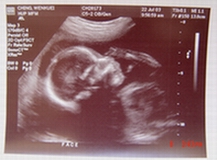

寶寶相片

昨天收到新買的數位相機,稍微研究一下,拍了幾張相片,來貼貼看。 這是寶寶21週4天時的相片。